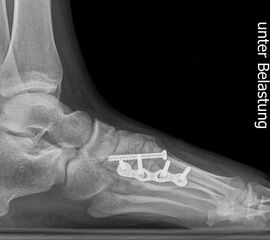

Röntgen

Standard ist die belastete Röntgenaufnahme des Fußes dorso-plantar und seitlich. Günstig ist eine Röhrenkippung von 10°-20°, um die Gelenke der Lisfranc-Linie einsehen zu können.